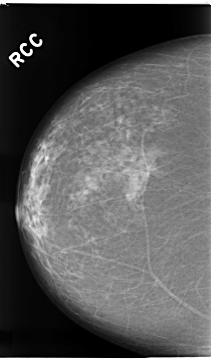

C_0112_1.RIGHT_CC

RIGHT_CC LINES 4672 PIXELS_PER_LINE 2736 BITS_PER_PIXEL 12 RESOLUTION 50 NON_OVERLAY